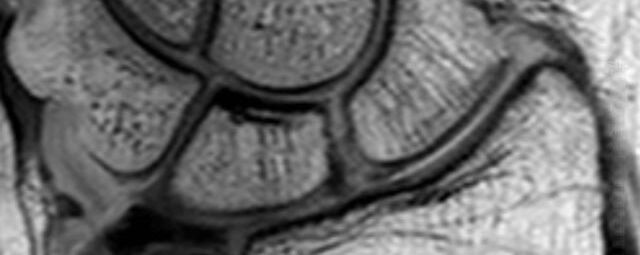

Hand

• Beurteilung von Knochen, Bändern und anderen Weichteilstrukturen der Gelenke nach Unfall.

• Arthrosediagnostik (Knorpelschaden)

• Impingement-Symptomatik

• Ursachenklärung bei wiederholter spontaner Gelenkluxation

• Ausbreitungsdiagnostik bei Gelenkentzündung, z.B. im Rahmen von rheumatischen Grunderkrankungen

Arthrographie

• MR-Arthrographie – nach örtlicher Betäubung und gründlicher Desinfektion der Haut wird unter Lagekontrolle mit Röntgen-Durchleuchtung eine kleine Nadel in den Gelenkraum positoniert und darüber ein MR-taugliches Kontrastmittel in den Gelenkraum gespritzt. Danach wird die Nadel entfernt. Anschließend erfolgt die MRT des Gelenkes. Diese Methode stellt kleine anatomische Strukturen des Gelenkraumes verbessert dar, z.B. zur Therapieplanung vor Arthroskopie bei Sportverletzungen der Schulter oder Gelenkinstabilität.